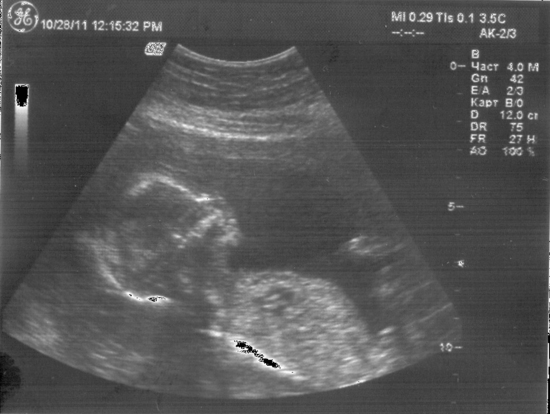

Вот и прошли мы наконец последнее долгожданное УЗИ. Толком посмотреть ребёночка не получилось...Повернулся личиком во внутрь и бултыхает ручками и ножками.... )))) Зато хорошо показал попку и писю...))) Подтвердилось что будет мальчик!

Наши данные такие:

БПР - 81мм

ОЖ - 293мм

ЛЗР - 104мм

ОГол - 292мм

ДБ - 62мм

Плацента 2-ой степени зрелости, толщиной 29мм расположена по передней стенке. Нижний край в 44мм от 3 зева.

Развалился!!! Ножки сложил, еще бы ручку под головку положил и вообще смешно было бы!!! А писюн то как торчит!!!

Наконец дождалась дня узи!!!

Бипариетальный размер: 39мм

Лобно-затылочный размер: 46мм

Окружность животика: 130мм (самый большой!!!) Пузатик!!! )))

Длина бедренной кости: 23мм

Размер малыша: 130мм

наш колобочек!!!!

А самое главное это пол!!! У нас будет мальчик!!! Наш папа на 7 небе от счастья!!!